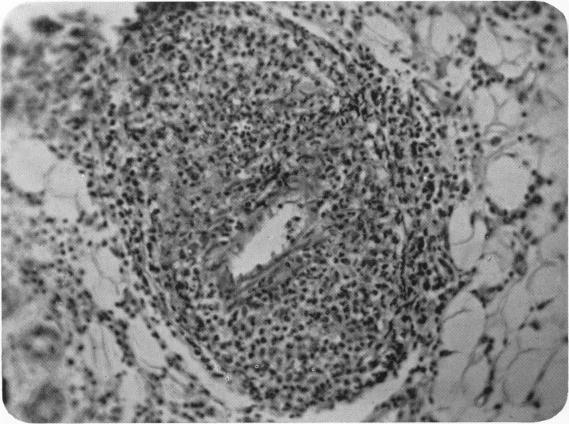

A case of periarteritis nodosa with subcutaneous lesions and recovery.

Arch Dis Child. 1938 Mar;13(73):31-44. doi: 10.1136/adc.13.73.31.